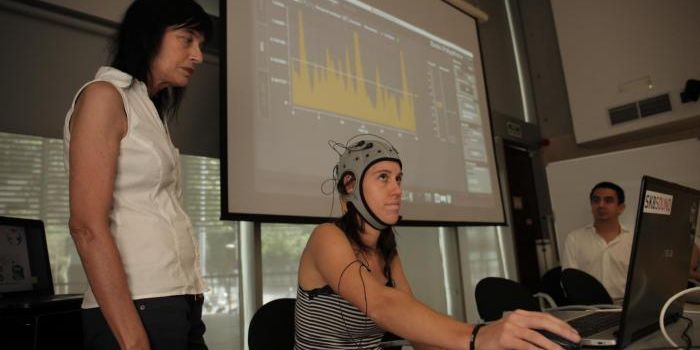

MAY 18, 2016NeuroscienceCan you move things with your thoughts? As it turns out, some people can, but they are not carnival performers or nightc ...